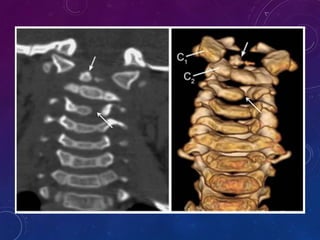

OS ODONTOIDEUM

• Failure of basal dental and axis body ossification centers to fuse at LS.

• Non-fusion is below the level of transatlantal lig - a/w instability.

• Orthotopic and dystopic (Os avis).

• Radiographic features:

• Smooth, well-corticated ossicle at the superior ossicle of a hypoplastic dens

• around half the size of a normal dens

• a/w hypertrophied and rounded anterior arch of the atlas

• Posterior arch is hypoplastic

43

• #46 Coronal 2D CT through plane of os odontoideum. The ossicle has defined cortical borders. There is a gap below it and a hypoplastic dens present. i Midsagittal T2-weighted MRI of CVJ. The cervicomedullary junction is draped over the superior axis body. Note the cruciate ligament in front of the axis; below the ossicle.